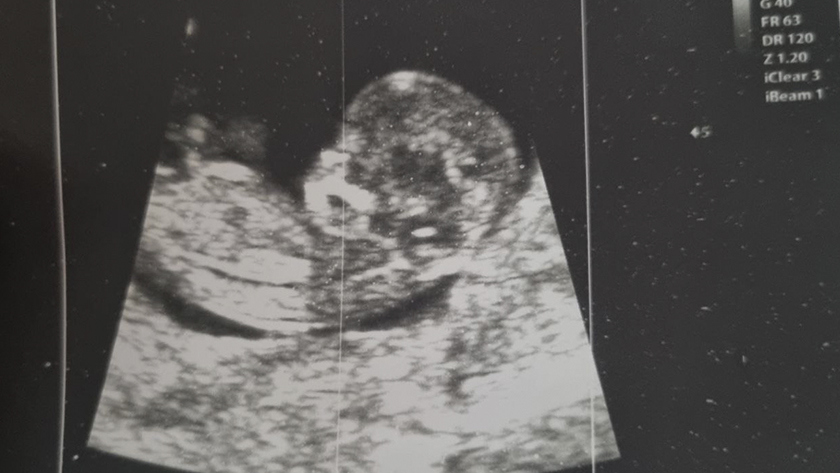

За одну беременность женщины могут трижды подать заявление о компенсации за проезд. Первые две поездки амурчанки делают пренатальные скрининги, которые необходимы при вынашивании ребенка, а с третьей поездки они возвращаются домой с малышом.

В 2025 году из регионального бюджета в рамках нацпроекта «Семья» выделено еще около шести миллионов рублей на эти цели. При этом медики просят северянок не игнорировать обследования. Особенно важен первый скрининг, который проводят с одиннадцатой недели беременности. По нему могут выявить хромосомные патологии у малыша. Не менее важна и вторая процедура, предполагающая определение у ребенка врожденных пороков.